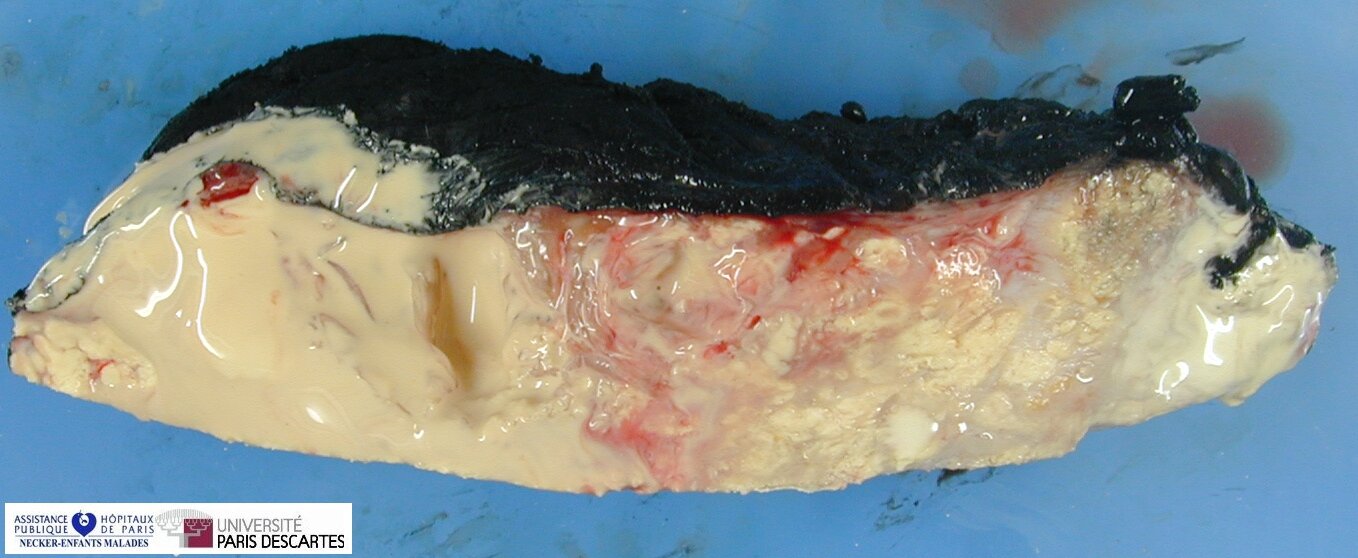

Tumoral Calcinosis